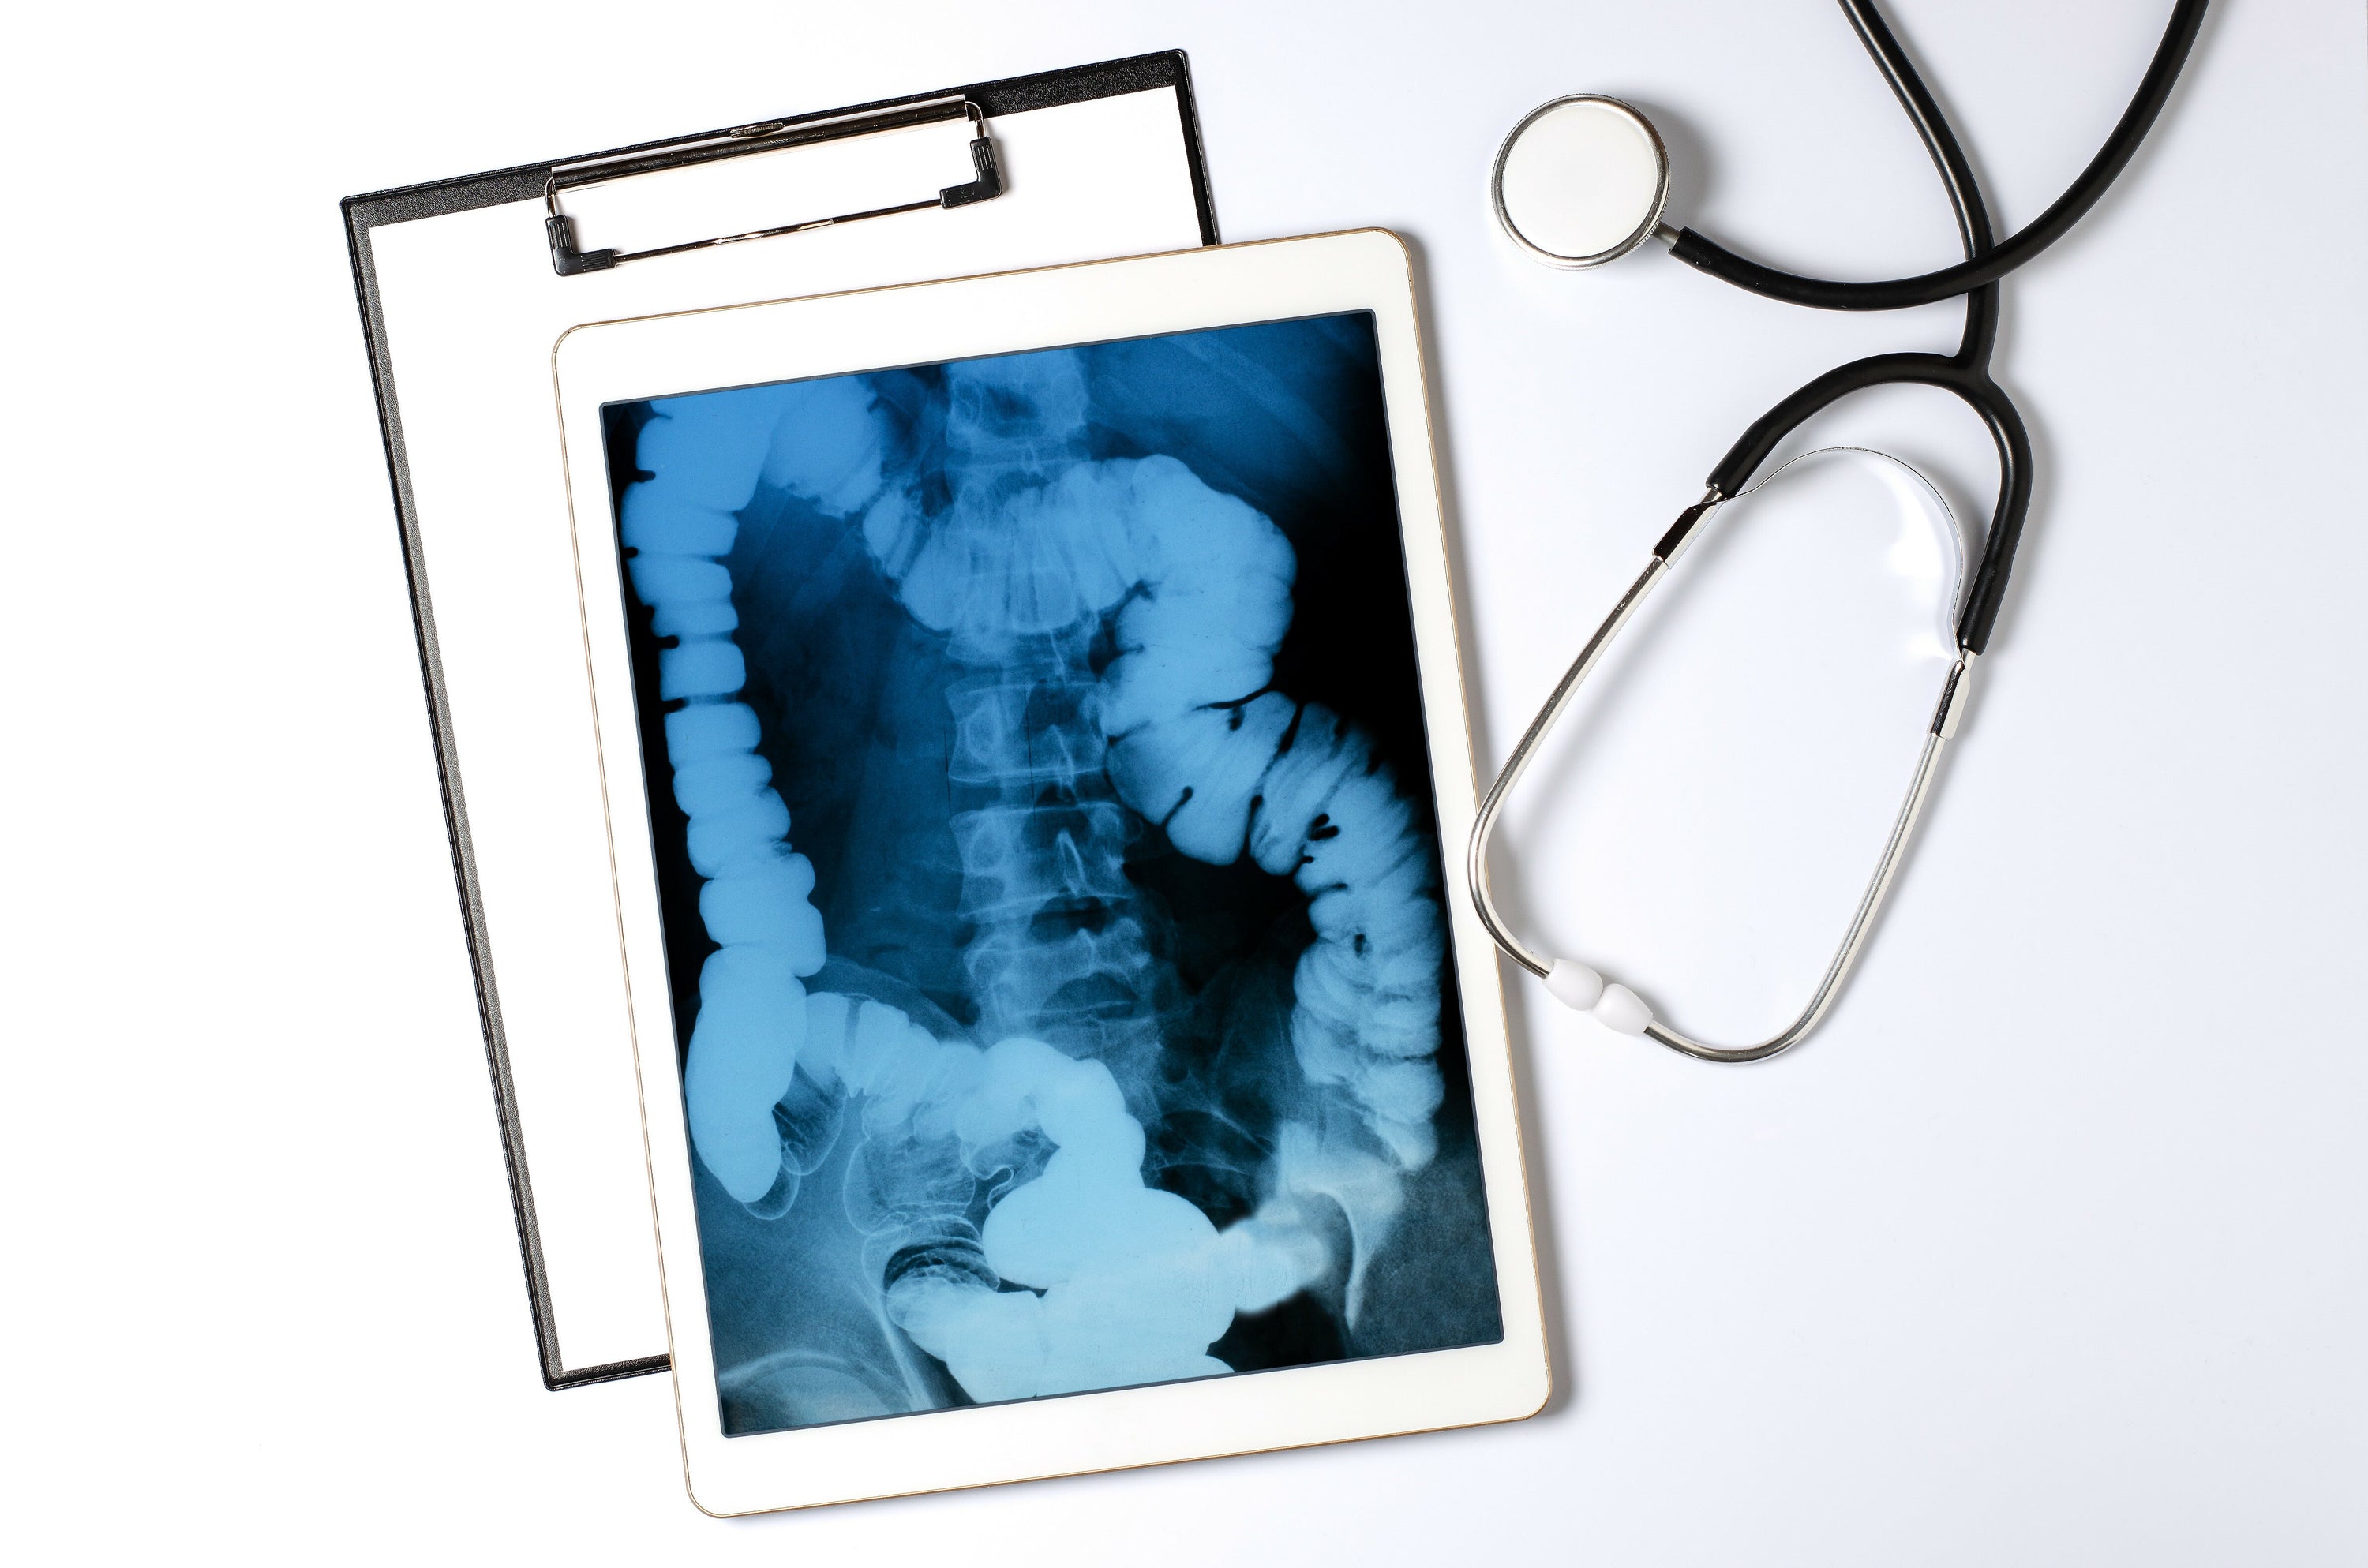

The function of an X-ray machine is to create an image of something that lies beneath an opaque surface. In a classic medical X-ray machine, it essentially involves a tube that shoots electrons at a piece of metal. When the electrons hit, X-rays are produced and passed through the body being examined.

Since different materials absorb the rays differently, an image is created on a detector or photographic plate. Bones appear white, soft tissues in shades of gray, and air appears black. Nowadays, digital X-ray techniques can directly convert these rays into images displayed on a screen. This modernization allows for immediate assessment of the imaging by the medical professional.

Understanding anatomy through X-rays of bones

What’s remarkable about X-rays is how they reveal the hidden structures of our bodies. They enable doctors to diagnose fractures, locate foreign objects, or assess the health of joints. X-rays are not limited to the human body; they also provide insights into the anatomy of animals, which is essential for veterinary diagnoses. X-ray imaging fascinates not only medical professionals but also the general public, as it makes visible what is invisible to the naked eye.

The importance of X-rays for diagnosis

X-rays are often the first step in the diagnostic process. Without them, a fracture might only be guessed. The anatomical images from an X-ray can reveal conditions that are not detectable through external examination methods. These include the presence of tumors, the extent of an infection, the presence of a bone injury, or the stage of a disease. Interpreting X-ray images requires expertise, as anomalies in bones and other parts of the human anatomy are not always easy to recognize and interpret. Your specialist will explain your X-ray results in detail and recommend further treatment.